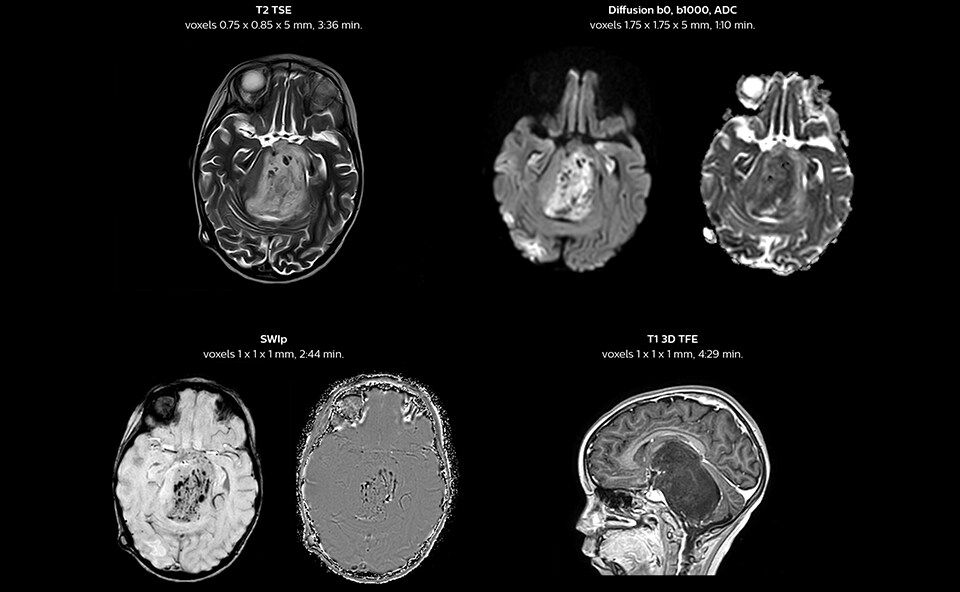

“We have been very, very pleasantly surprised by the quality of the images,” says Dr. Mahajan. “I have shown Prodiva images to people around the world during my travels.” Ingenia Prodiva 1.5T includes such features as dStream digital broadband technology to increase image quality with high SNR. “The system came with its newest sequences that allow us to perform advanced techniques like excellent diffusion in the brain and other body parts as well, spectroscopy, detailed neurography, CSF flow studies, imaging of difficult areas like skull base, tractography, DTI, and even DTI of the spinal cord – all of this is available to us.” The radiologists at Mahajan Imaging were also impressed by the quality of cardiac MRI. “We have done some MR angiography of the coronary arteries with the Prodiva and it provided excellent coronaries – and this was without using any contrast agent. We can also perform fantastic ngiography of other body parts.” “With Prodiva 1.5T, the images are very crisp and sharp, and the resolution is very good,” says Dr. Mahajan. “Imaging can be done in short scan times with excellent quality and broad range of possible applications, whether it is angiography, a scan with 3D reconstruction, any kind of more special images, what we do, the sharpness, resolution and the ease of use – everything counts in total when we are reporting.”